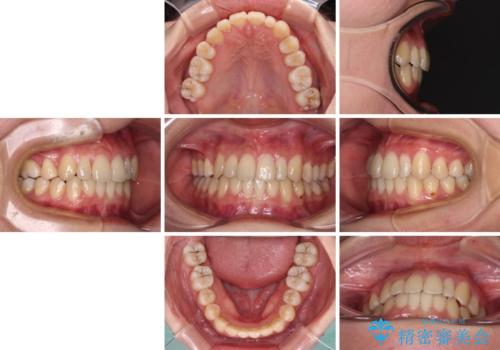

八重歯の抜歯矯正 補助装置を用いたインビザライン矯正

- 上顎の重なっている前歯を気にして来院された患者様です。

重なっている部分は抜歯が必要で、歯の移動量が多く、更には右側にずれている正中を改善する必要がありました。

インビザライン単体での治療は困難と判断し、補助装置により八重歯移動後にインビザラインを用いることとしました。

非常にしっかりとマウスピースを装着してくださいましたが、前歯の排列がなかなか仕上がらずに期間がかかってしまいました。